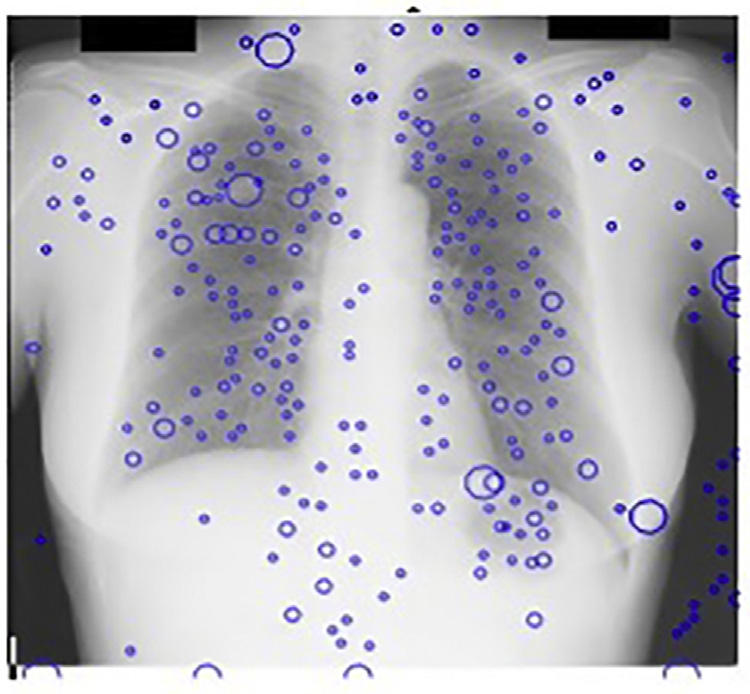

尽管胸部X光在临床日常中提供了重要的诊断检查,但由于相关诊断结构与无关的骨性结构重叠,使得影像较为复杂。因此,当前计算机辅助诊断系统(科皮尼、迪乔蒂、法尔基尼、维拉里和瓦利,2003年;吉格尔、土井、麦克马洪、梅茨和尹,1990年;德科宁等人,2013年;兰格、普拉特和因巴尔,1997年)在胸部X光片中面临的主要挑战是检测与肋骨、肋骨交叉及锁骨重叠的结节,如图14.1所示。这些骨性结构会导致大量的假阳性结果,正如凯瑟尔奇和吉田(2002年)所指出的

使用主成分分析滤波器进行肋骨抑制的结果如图14.2B所示。采用标准的高斯检测器高斯拉普拉斯掩模(LOG)来寻找可能存在结节的峰值区域。在原始胸部X光图像中应用该掩模导致了大量的假阳性,如图14.2A 所示,其中许多假阳性出现在肋骨上。